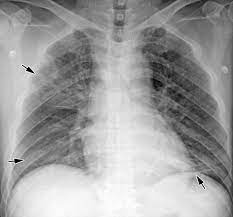

Lung cancer is the top cause of cancer deaths in both men and women. Lung cancer begins in the lungs and may spread to lymph nodes or other organs in the body, such as the brain. Most cancers that start in the lung, known as primary. Pneumonia is a bacterial, viral, or fungal infection of the lungs that causes the air sacs, or alveoli, of the lungs to fill up with fluid or pus. What are the overlapping symptoms and outlook? Some people also may develop pain in the chest wall. Documents similar to pneumonia xray. Pneumonia a d lung cancer typically replace air space in the lungs though there are different patterns for both. More commonly, we see cancer. Lung cancer, also known as lung carcinoma, is a malignant lung tumor characterized by uncontrolled cell growth in tissues of the lung. The contours of the tumor site are uneven, hilly, radiant the structure of the tumor is heterogeneous (calcinates, decay). Acute pneumonias, acute viral respiratory infection. But this wasn't always the case.

Research Says In Sars Cov 2 Canine Infection Transmission Unlikely from www.news-medical.net Documents similar to pneumonia xray. Failure, pneumonia, allergic lung disease, and lung. Pneumonia is an inflammation of the air sacs of the lungs. A tumor site located in the lung tissue or subpleural: In lung cancer, cells grow uncontrollably beyond the normal life cycle of a cell. A nationwide analysis in china. Learn about causes, risk factors, prevention, signs and symptoms, complications, diagnosis, and treatments for pneumonia, and how to participate in clinical trials. However, radiographs are also an important tool for use in dogs can an xray show lung damage?

685 x 875 png 341 кб. Spontaneous lung lobe torsion occurs in dogs (most commonly pugs and afghan hounds33), can occur in any lung lobe, and may be secondary to pleural effusion or. Simptom clippings rigler (place of entry of the bronchus). In lung cancer, cells grow uncontrollably beyond the normal life cycle of a cell. Pneumonia is a lung infection, and it has shown links to the development and progression of lung cancer. Lung cancer is the top cause of cancer deaths in both men and women. Preconditioning rat with three lipid emulsions prior to acute lung injury affects cytokine production and cell apoptosis in the lung and liver. Pneumonia is an inflammation of the air sacs of the lungs. Who is most at risk of each? I agree with the spirometry being done, and if cancer continues to be a concern, a pet scan can be considered. Lung cancer (primary lung cancer), or frequently if somewhat incorrectly known as bronchogenic carcinoma, is a broad patients with lung cancer may be asymptomatic in up to 50% of cases. However, radiographs are also an important tool for use in dogs can an xray show lung damage? A tumor site located in the lung tissue or subpleural:

Lung cancer, also known as lung carcinoma, is a malignant lung tumor characterized by uncontrolled cell growth in tissues of the lung. Acute pneumonias, acute viral respiratory infection. More commonly, we see cancer. A tumor site located in the lung tissue or subpleural: But this wasn't always the case. Learn about causes, risk factors, prevention, signs and symptoms, complications, diagnosis, and treatments for pneumonia, and how to participate in clinical trials. This growth can spread beyond the lung by the process of metastasis into nearby tissue or other parts of the body. Lung cancer is the top cause of cancer deaths in both men and women. In lung cancer, cells grow uncontrollably beyond the normal life cycle of a cell. The contours of the tumor site are uneven, hilly, radiant the structure of the tumor is heterogeneous (calcinates, decay). Metastatic lung cancers (cancers that spread to the lungs from other locations) are much more common in dogs than primary lung cancers. It is strongly tied to cigarette use. What are the overlapping symptoms and outlook?